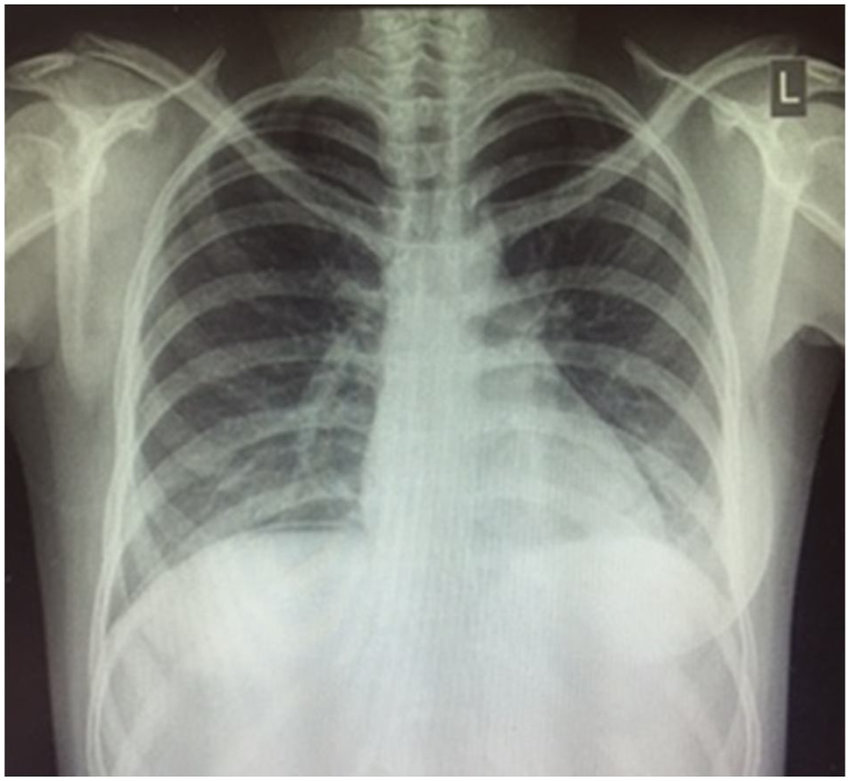

Image courtesy of https://www.researchgate.net/figure/Erect-chest-x-ray-demonstrating-subdiaphragmatic-free-air_fig1_323084315